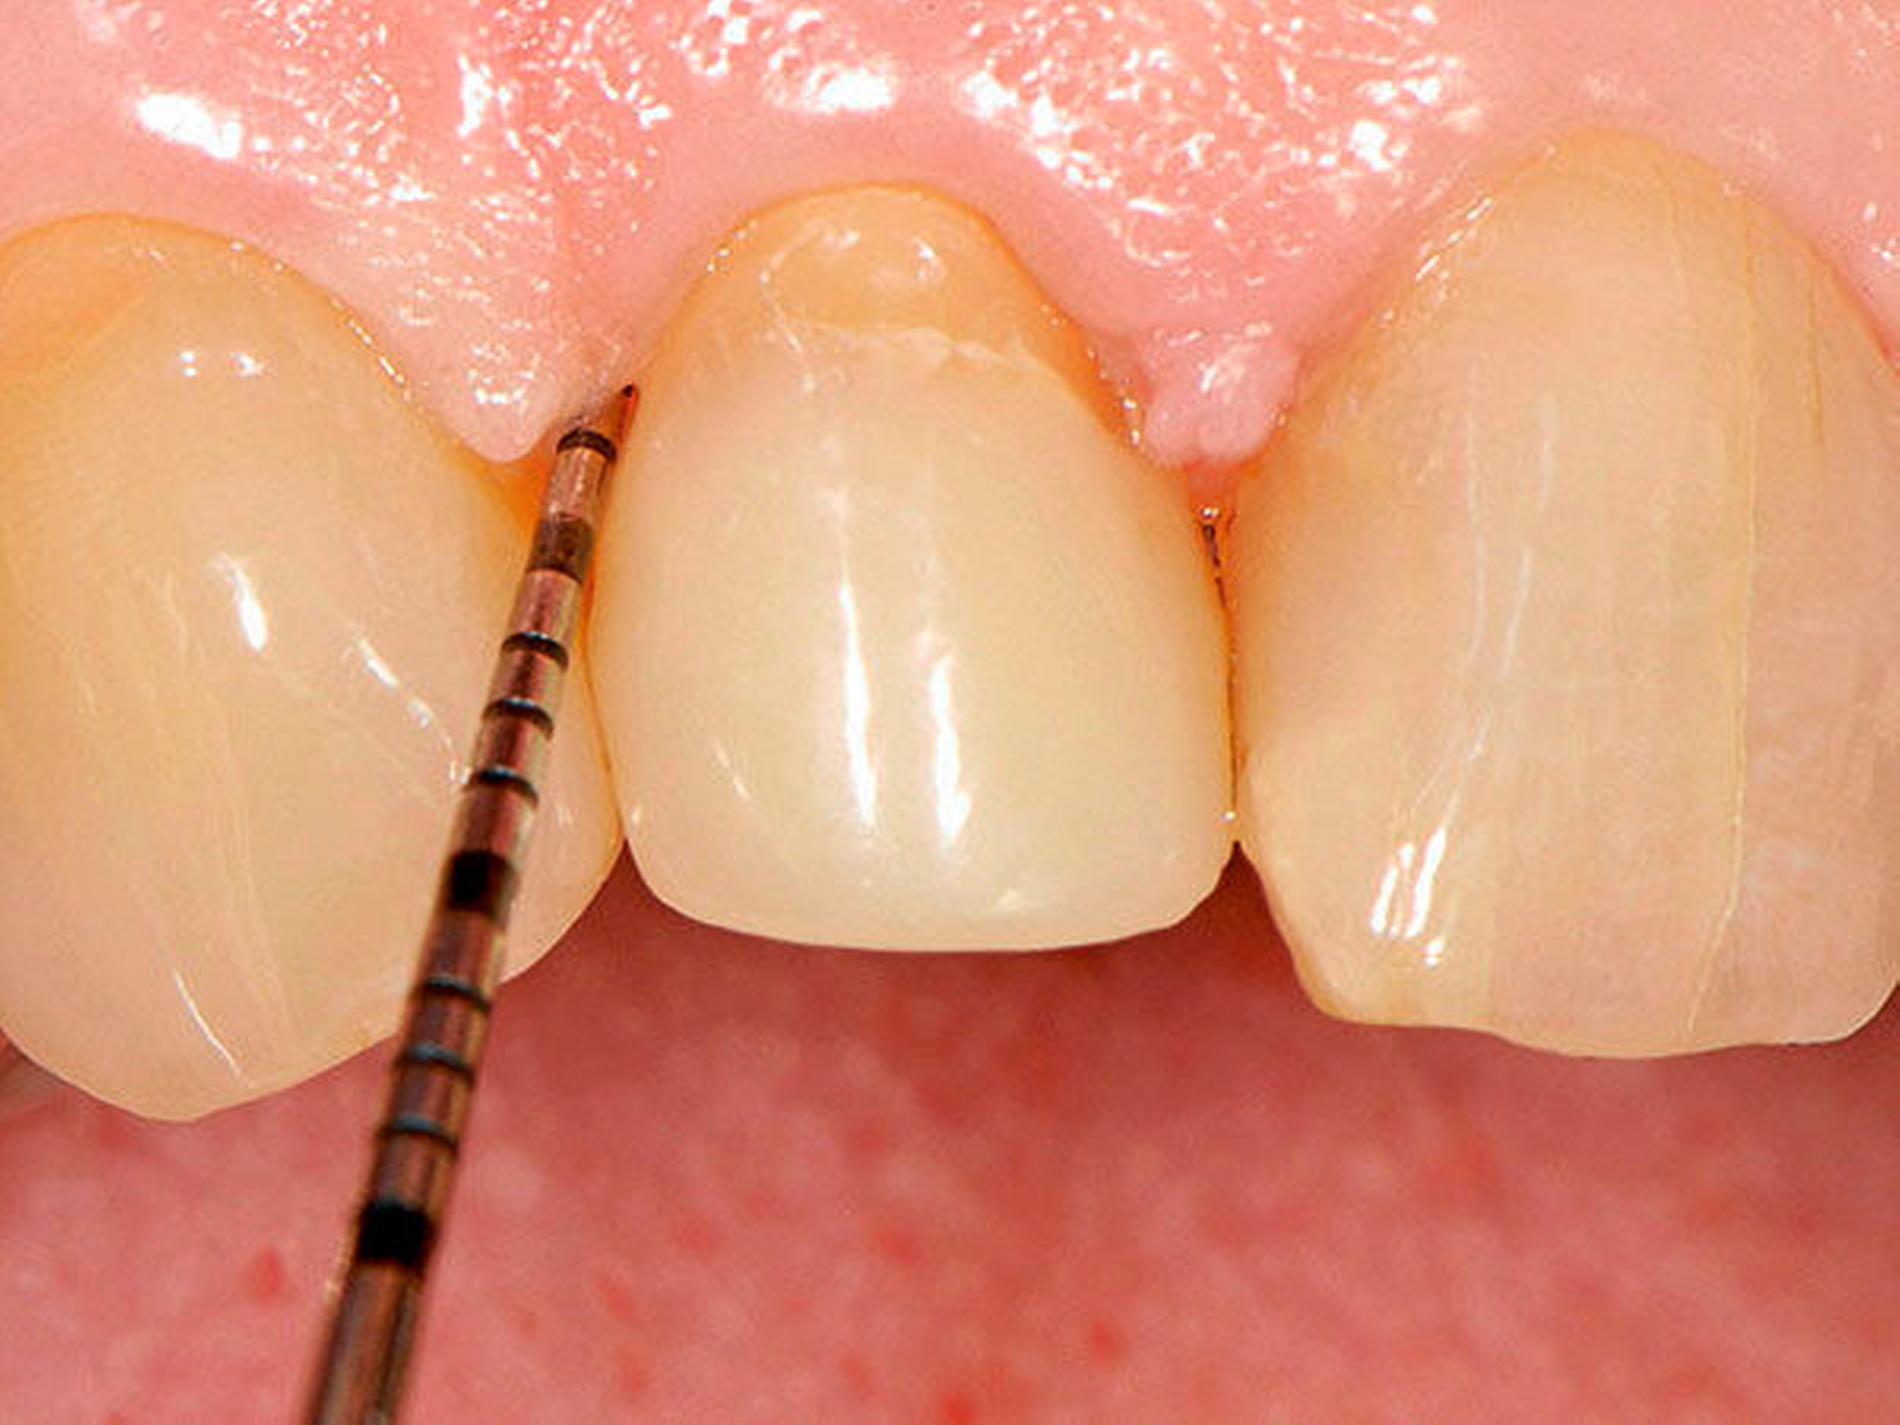

Abbildung 4: Überwachtes Monitoring (Belassen und Beobachten) von Zahnlücken

In der Zahnmedizin ist ein Dogma weit verbreitet: „Jede Lücke muss rasch geschlossen werden.“ Tatsächlich gibt es jedoch viele Situationen, in denen es ohne relevante funktionelle und ästhetische Einbußen vertretbar erscheint, eine Lücke zu belassen und regelmäßig zu beobachten (Monitoring). Derzeit erfolgt die Entscheidung „Lücke belassen versus Lücke schließen“ oftmals subjektiv. Sie ist zuweilen weniger von den Patientenvariablen abhängig als von den Schwerpunkten der betreuenden Zahnärzte (Abbildung 4) [Listl et al., 2016]. Ein fachlich fundiertes Vorgehen, das eine Entscheidung unter einer Nutzen-Risiko-Abwägung trifft und ein Monitoring in die Überlegungen einbezieht, kann ebenfalls in die Kategorie der frugalen Interventionen eingeordnet werden. Gleiches gilt für ein Vorgehen im Sinne des Prinzips der verkürzten Zahnreihe, das inzwischen wissenschaftlich gut evaluiert ist [Walter, 2016] und zu dessen Realisierung auch konservierende Maßnahmen beitragen können (Abbildung 5).

Falls ein Lückenschluss nach Gegenüberstellung der Vor- und Nachteile als angemessen angesehen wird, stellt sich die Frage, mit welchen Hilfsmitteln dies erfolgen soll. Derzeit stehen Implantate und klassische Brückenversorgungen im Vordergrund. Es gibt aber auch etliche nicht- oder minimal-invasive Alternativen, die zum Beispiel bei Einzelzahnlücken in Erwägung gezogen werden können. Dazu zählen unter anderem direkte Verfahren wie Zahnverbreiterungen oder -anhänger (Abbildungen 6 und 7) [Staehle, 2009 und 2012; Staehle et al., 2015]. Zurzeit kommen derartige Maßnahmen nur in Einzelfällen in Betracht, es bedarf noch weiterer Evaluationen, um ihr Indikationsspektrum genauer abgrenzen zu können. Es zeichnet sich aber jetzt schon ab, dass sie ein gewisses Potenzial als frugale Interventionen besitzen. Auch wenn momentan vielfach Implantate favorisiert werden, erscheint es dennoch sinnvoll, wenn die Zahnärzteschaft auch diverse Implantat-Alternativen vorhalten kann. Ungeklärte Probleme periimplantärer Entzündungen [Chrcanovic et al., 2016] und die zu erwartende Diskussion über Beziehungen zwischen periimplantären Entzündungen und der Allgemeingesundheit lassen es als sinnvoll erscheinen, solchen Fragen intensiver als bisher nachzugehen. Bislang wird zwar nur über Einflüsse der Allgemeingesundheit auf den Erfolg beziehungsweise Misserfolg von Implantaten diskutiert. Es ist aber nicht auszuschließen, dass man künftig die Fragestellung in umgekehrter Richtung dahingehend erweitert, inwieweit Implantate ihrerseits nicht nur positiven, sondern auch negativen Einfluss auf die Allgemeingesundheit nehmen können.